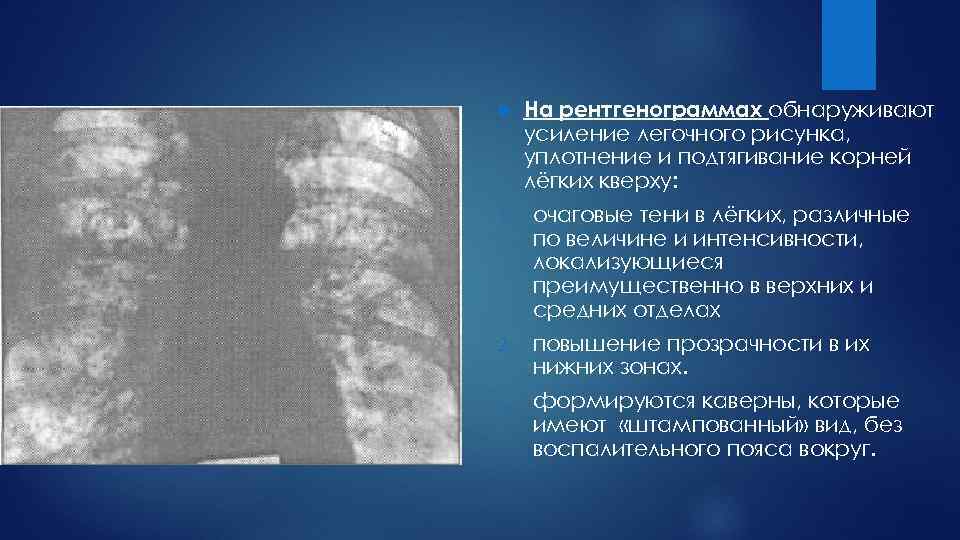

Рентгенологические изображения и синдромы патологии легких

Раздел: Кадры-подсказки